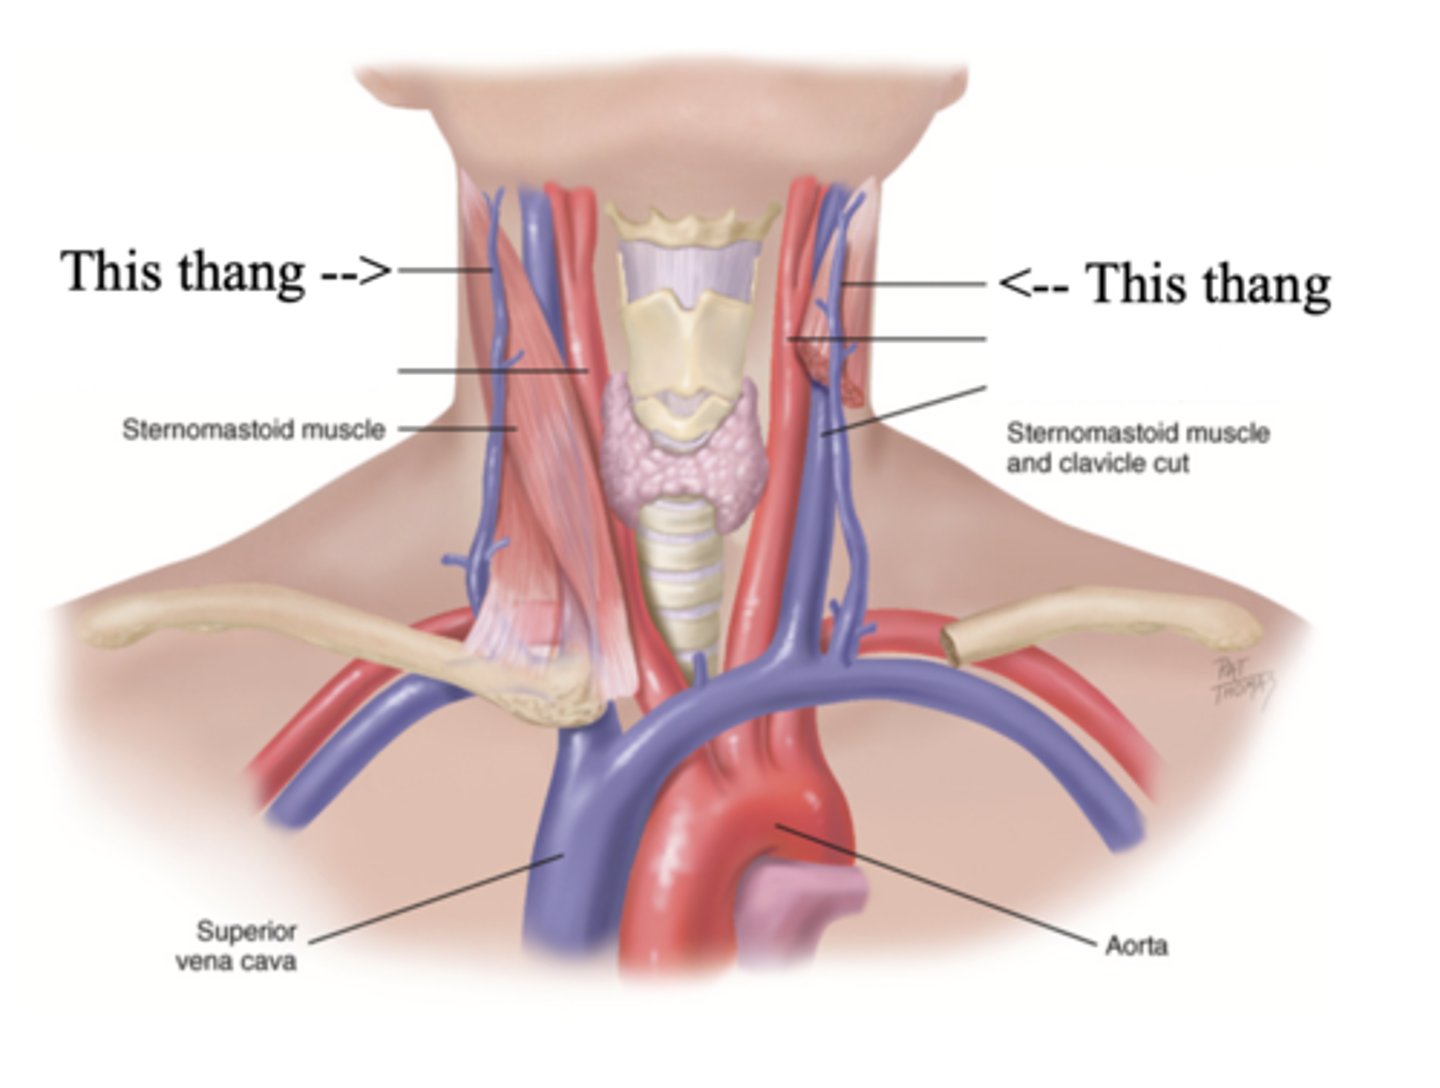

2 Main Neck Vessels

- Jugular veins

- Carotid arteries

Jugular Veins

- One of the main neck vessels; carries unoxygenated blood to the superior vena cava

- Has 2 parts

- Provides information about activity of right side of heart

2 Parts of the Jugular Veins

- External

- Internal

External Jugular Veins

The more superficial jugular vein that lies lateral to the sternocleidomastoid and above the clavicle

Internal Jugular Veins

The deeper jugular vein that lies medial to the sternocleidomastoid

Carotid Arteries

The major neck vessel that carries oxygenated blood from the heart to the head

Main Differences Between Internal Jugular Veins and Carotid Arteries

- Internal jugular pulse more lower and lateral to sternocleidomastoid than the carotid pulse, which is higher and more medial

- Internal jugular pulse is more undulant and diffuse, while carotid pulse is more brisk and localized

- Internal jugular pulse varies with respiration

- Carotid pulse can be palpated

- Palpating internal jugular pulse will obliterate it

- Internal jugular pulse drops/disappears as the patient is brough to a sitting position